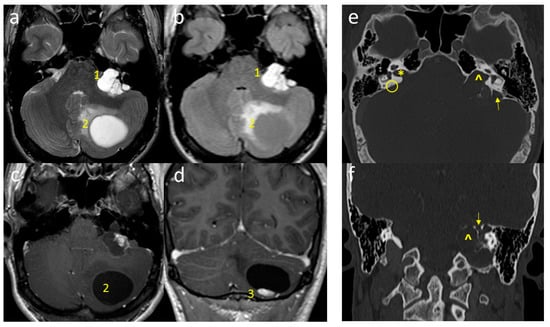

2. Case Report